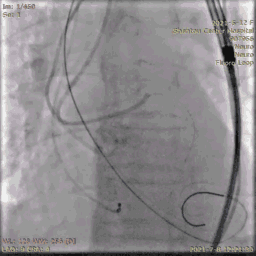

送入输送系统

输送系统定位

输送系统定位,标准位置释放

120bpm起搏

轻微反流,压差降低

25球囊后扩

无瓣周漏